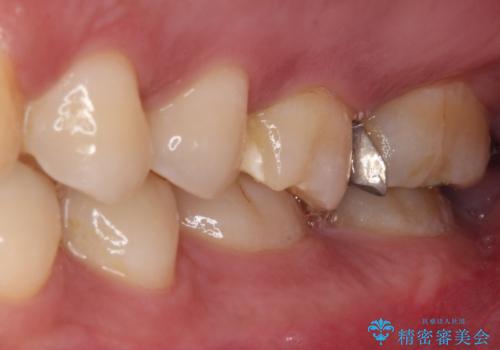

ゴールドインレーは銀歯のインレーやセラミックインレーと比べ、「技工操作の精度が高く、適合が著しく良い」というメリットがあります。特に上の奥歯は歯科医師の操作が行いにくいため、「適合の良さ」は再治療のリスクを防ぐ上でとても重要な要素となります。

上の奥歯は金属色が見えることもないため、審美的な問題は全くありません。